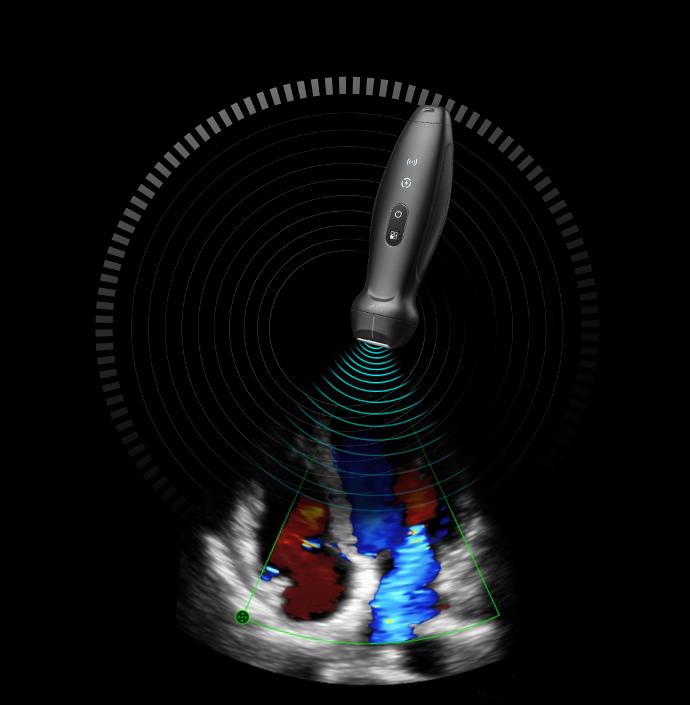

- Безжичен джобен ехограф/сонда TE Air i3P Mindray

TE Air е новото поколение безжична ултразвукова система на Mindray, е проектирана да отговори на тези по-високи клинични изисквания. Чрез съчетаване на премиум функционалности с безжично изживяване, ефективна свързаност и здрава конструкция за непредвидени среди, TE Air помага да се подобри увереността и ефективността на лекарите по начини, които преди са били немислими.

Премиум възможности в джобен формат

Джобен ехограф от ново поколение

Осигурен от платформата eWave и технологията от второ поколение Single Crystal, TE Air предоставя висококачествени изображения с ниска консумация на енергия за точно вземане на решения.

Лесен за използване, навсякъде

Лек и безкабелен

Дава изключителното удобство за преглед без кабел или тежък апарат. Джобният TE Air работи само с мобиленият Ви телефон.